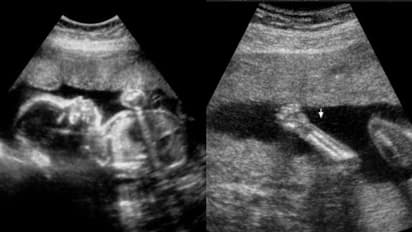

തിരുവനന്തപുരം: ഗർഭസ്ഥശിശുവിന്റെ വൈകല്യം കണ്ടെത്തുന്നതിൽ വീഴ്ച വരുത്തിയ സ്വകാര്യ ആശുപത്രി പലിശ സഹിതം 82 ലക്ഷം രൂപ നഷ്ടപരിഹാരമായി നല്കാൻ സംസ്ഥാന ഉപഭോക്തൃ കമ്മീഷന്റെ ഉത്തരവ്. ഭ്രൂണത്തിന് അരക്ക് താഴോട്ട് വളർച്ചയില്ലെന്ന് സ്കാനിങ്ങിലൂടെ കണ്ടെത്തുന്നതിൽ പരാജയപ്പെടുകയും സ്കാനിങ് റിപ്പോർട്ടിൽ കൃത്രിമം കാണിക്കുകയും ചെയ്ത ആശുപത്രി അധികൃതർക്ക് രൂക്ഷ വിമർശനത്തോടെയാണ് കമ്മീഷൻ്റെ തീരുമാനം. ഇല്ലാത്ത കാലുകളുടെ തുടയെല്ലിന്റെ നീളം ആണ് സ്കാനിംഗ് റിപ്പോർട്ടുകളിൽ രേഖപ്പെടുത്തിയിരിക്കുന്നത്. വിദേശ മലയാളി ദമ്പതികളായ ജയേഷ്, രശ്മി ദാസ് എന്നിവരുടെ പരാതിയിലാണ് 8 വർഷത്തിനു ശേഷം വിധി വന്നിരിക്കുന്നത്.

സ്കാനിങ്ങിൽ പ്രത്യേകിച്ച് തകരാറൊന്നും കണ്ടെത്താൻ കഴിയാഞ്ഞത് കൊണ്ടാണ് വിശദമായ അനോമലി സ്കാനിംഗ് നടത്താഞ്ഞതെന്നാണ് കുറ്റാരോപിതരായ ഡോക്ടര്മാരായ കെന്നി എ തോമസും പ്രീത ബിജുവും വാദിച്ചത്. അനോമലി സ്കാനിംഗ് നടത്താഞ്ഞത് ആശൂപത്രിയുടെ വീഴ്ചയായി കമ്മീഷൻ കണ്ടെത്തി. മാത്രമല്ല റേഡിയോളജിസ്റ് നടത്തേണ്ട സ്കാനിംഗ് അതിൽ പ്രാവീണ്യമില്ലാത്ത ഒരു ഡോക്ടറാണ് ചെയ്തത്. അമ്നിയോട്ടിക് ഫ്ലൂയിഡിന്റെ കുറവുണ്ടായത് കൊണ്ടാണ് വൈകല്യം അറിയാൻ പറ്റാഞ്ഞതെങ്കിൽ ഫ്ലൂയിഡിന്റെ കുറവ് സ്കാനിംഗ് റിപ്പോർട്ടിൽ രേഖപ്പെടുത്തേണ്ടതായിരുന്നു. ശിശുവിന്റെ ചലനത്തെക്കുറിച്ചു യാതൊരു കുഴപ്പങ്ങളും റിപ്പോർട്ടുകളിൽ പറഞ്ഞിട്ടില്ല. ഏറ്റവും ഗുരുതരമായ വീഴ്ച കാലുകൾ ഇല്ലാത്ത ശിശുവിന്റെ തുടയെല്ലിന്റെ നീളം റിപ്പോർട്ടുകളിൽ രേഖപ്പെടുത്തിയിരുന്നു എന്നതാണ്.